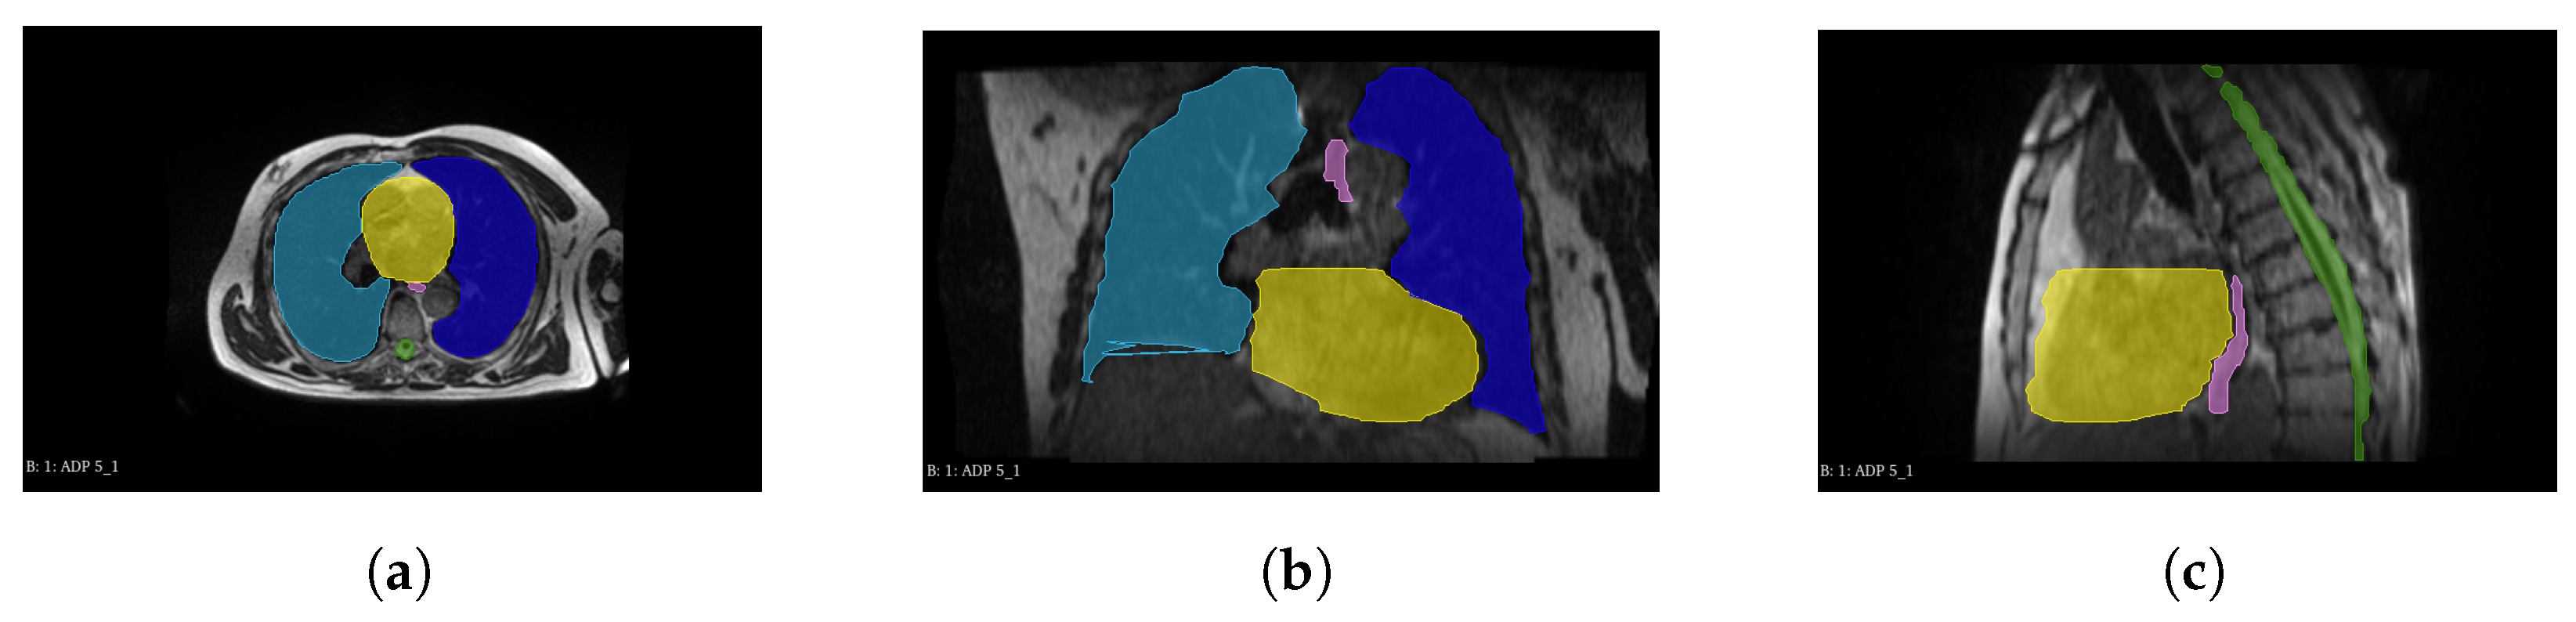

2.1. Dataset

2.2. Preprocessing